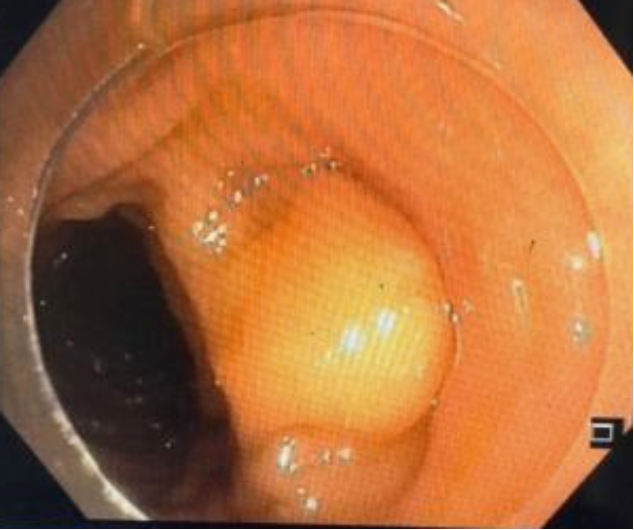

胃肠科手术室内消化专家宋国彬与护士姜士秀的紧密配合按照计划顺利实施手术,在粘膜下注射生理盐水2ml,粘膜切开刀环周切开,剥离后暴露瘤体,完整剥离后置3枚和谐夹缝合创面,历时2个小时的手术,术程顺利,无出血及穿孔。

术后